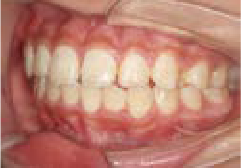

でこぼこ

でこぼこでも大丈夫。抜かずに、あごから育てる矯正治療

Jさん (矯正開始時:8歳)

Before

After

歯がガタガタに並んでいて、前歯の真ん中の位置が少し左にずれていました。

奥歯が生えるためのスペースが足りず、永久歯が生えて来られない状況が確認できました。

また、飲み込むとき下くちびるに力が入ってしまうクセが見られ、お顔全体の成長が遅れている様子が確認できました。

治療を終えて

歯がきれいに生えるためのスペースをしっかり確保することができ、歯並びを乱していたお口のクセも改善されたため、奥歯が生えるスペースを確保することができました。

しっかり噛めるかみ合わせを作ることが、将来の健康につながるので「よく噛む」練習も続けてもらっています。

主訴・治療内容 歯がガタガタになってきたことに悩み、無料相談に来院されました。

治療期間 3年

費用 462,000円(税込)